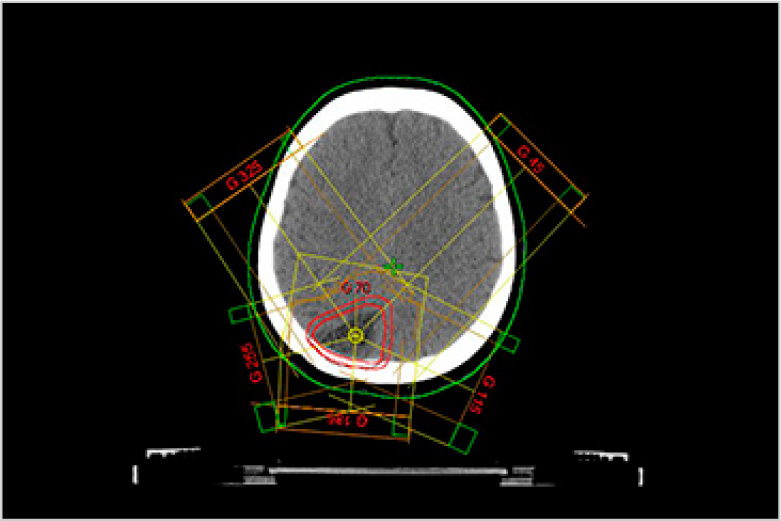

放射線治療とは身体できた病巣部に放射線を照射しがん等の病気を治す治療法です。

手術と比較し身体への負担が少なく病巣部を安全かつ効果的に治療することができます。

当院で使用する放射線は高エネルギーX線及び電子線で直線加速器(リニアック)を用いて人工的に放射線を作るため目的に応じた線質、強さ、量に調整することができます。

実際の治療ではまず治療開始前にCT撮影を行い、照射する場所、範囲、放射線の量等を専用の機器を用いて決定します。(下図参照)これをもとに治療時には装置に搭載されたX線撮影装置、CT装置にて画像を撮影し3次元的に位置照合を行い計画された方向より照射します。

治療装置は360度どの方向からでも照射可能で病巣を多方向から正確に照射することで治療効果の向上、病巣周囲の正常組織の線量を減らすことができます。

バリアン True Beam